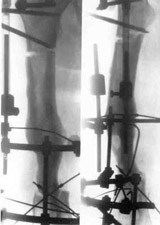

Patient in Ilisarov's apparatus.Patient in Ilisarov's apparatus.Patient in Ilisarov's apparatus.

Patient in Ilisarov's apparatus.